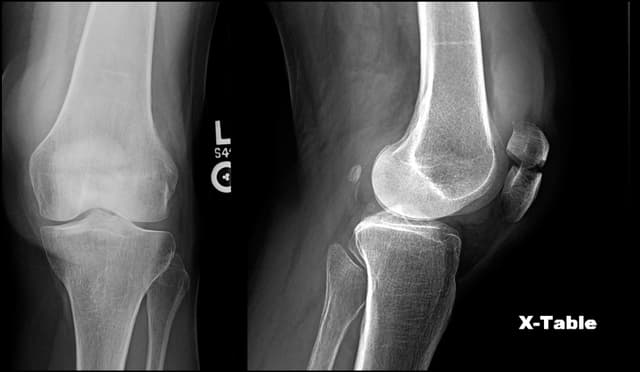

Patella ORIF

Pre-op

Post-op